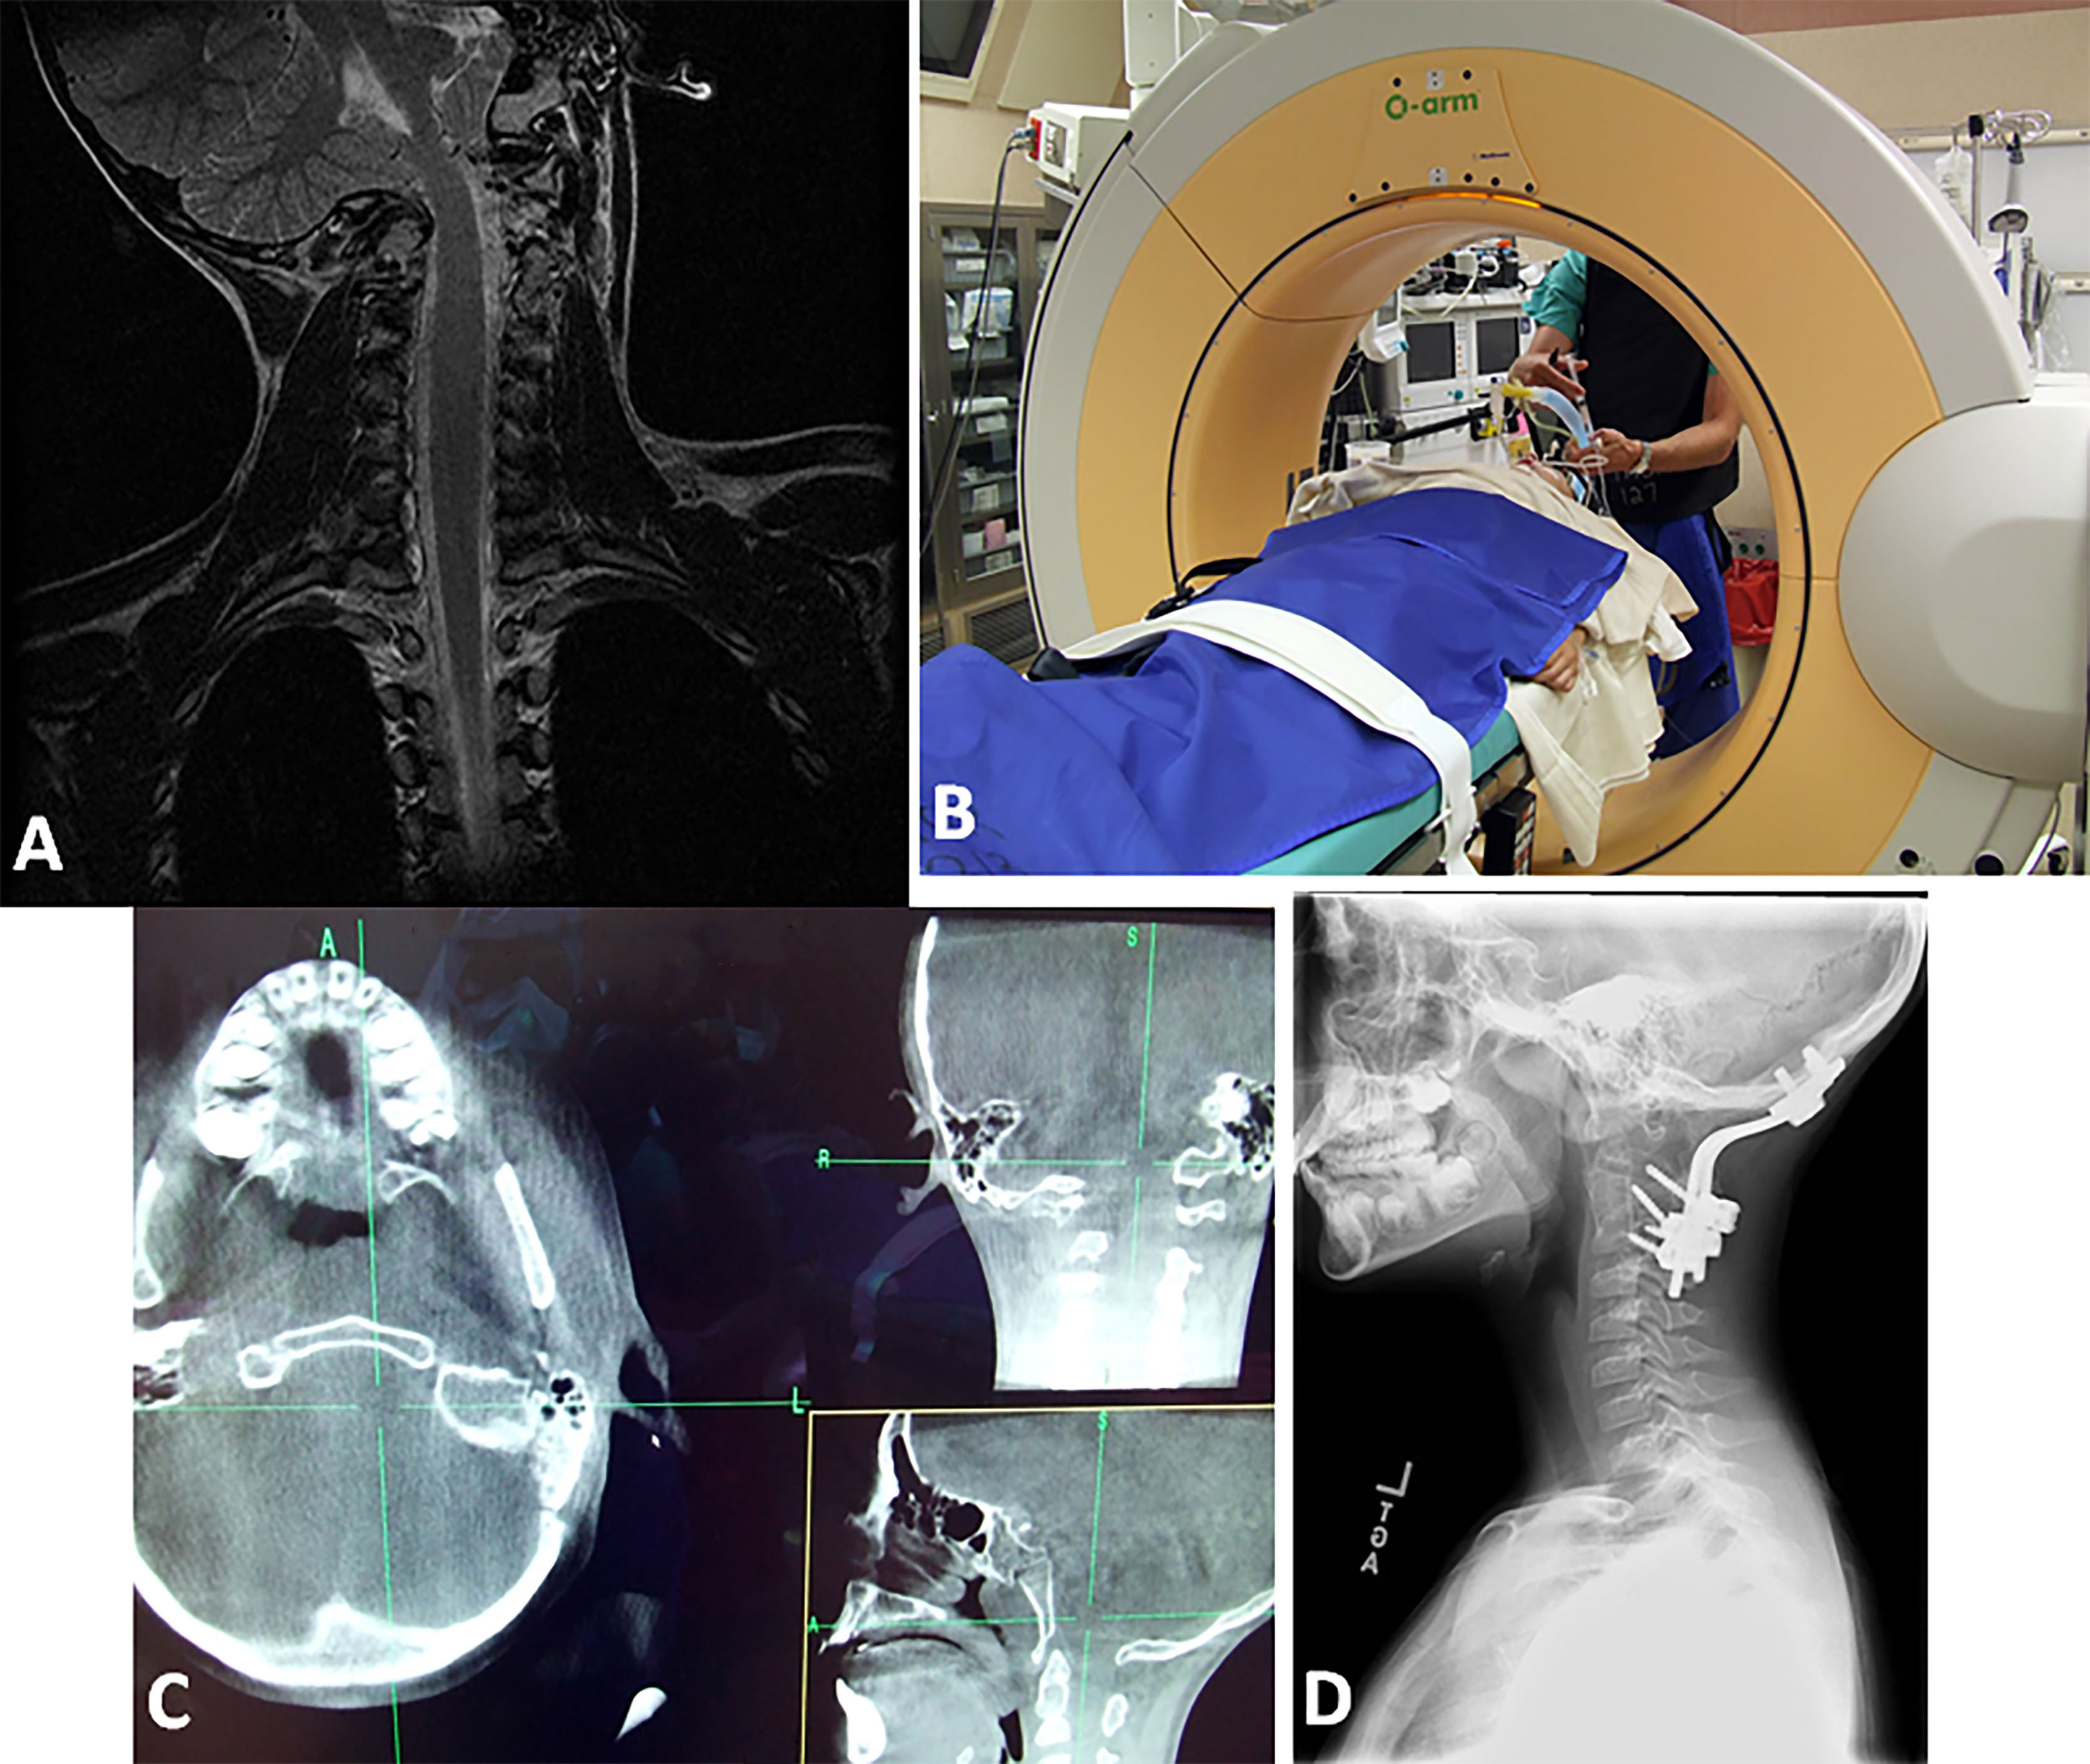

Figure 4: Case #4; A) Coronal T2-W MRI of craniocervical region. Note the O-C1 dislocation with cervicomedullary distortion. B) Anesthetized patient in O-arm CT in traction. C) Composite of axial, coronal and sagittal plane CT in the “O-arm” CT in traction. The rotary dislocation is reduced. D) Postoperative lateral cervical radiograph. There is a completed dorsal occipitocervical fusion.

Figure 5: Case #5; A) 3D CT of CVJ in lateral projection. Note the atlantoaxial dislocation. B) 3D CT of CVJ viewed from below. There is a rotary atlantoaxial luxation (jumped facet) (arrow). C) Axial T1-W MRI at C1-C2 level. Arrow points the disrupted transverse cruciate ligament. D) Intraoperative lateral craniocervical fluoroscopic image. The patient is in crown halo traction. The ET tube angle is > 110 degrees (arrows). The dorsal O-C2 fusion is made.

Figure 6: Case #6; Lateral CVJ T1-W MRI in midsagittal plane. There is atlas assimilation, severe odontoid invagination into the upper medulla, cerebellar tonsils to C2-3, and evidence of posterior fossa decompression with C1-C3 laminectomies.